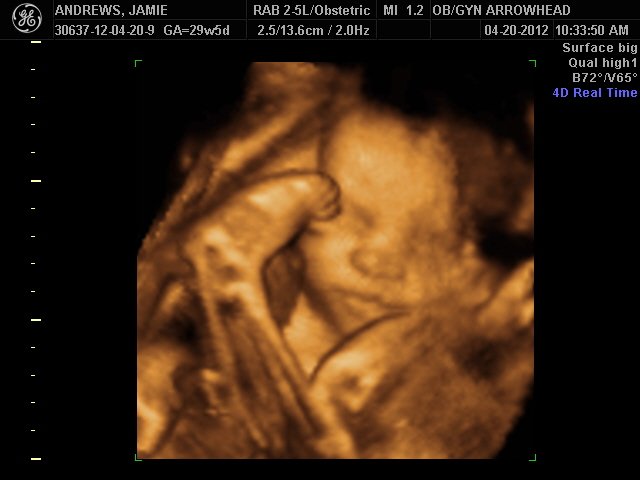

We offer complimentary 3D/4D Ultrasounds to all our OB patients around 30 weeks! The following photos are some examples of our work, shown with permission from our patients.